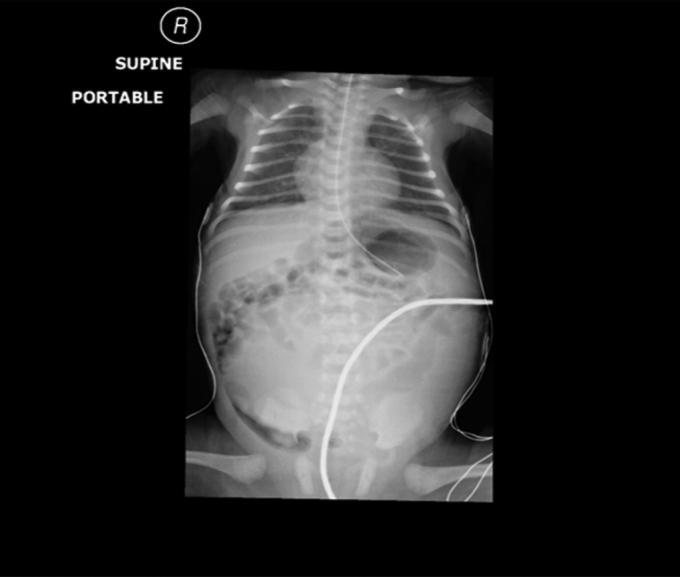

A 5 day old baby, with known left hydronephrosis which discovered by prenatal US presented with gastrointestinal tract obstruction. Laboratory work up demonstrated abnormal renal function and metabolic acidosis combined with hyperkalemia. Radiology tests showed bilateral hydronephrosis with huge left renal pelvis crossing the midline and causing deviation of the gut laterally. This acute presentation beside inability to receive oral feeding made us prefer immediate left renal drainage with pyelostomy in order to restore renal function, relieve the pressure effect of the huge renal pelvis and stabilize the baby. Dismembered pyeloplasty was done at age of 3 months.

一名5天大的婴儿,产前超声检查发现已知患有左肾积水,现出现胃肠道梗阻。实验室检查显示肾功能异常、代谢性酸中毒合并高钾血症。放射学检查显示双侧肾积水,巨大的左肾盂越过中线并导致肠道向外侧移位。除了无法经口喂养外,这种急性表现使我们倾向于立即进行左肾造瘘引流,以恢复肾功能、减轻巨大肾盂的压迫作用并使婴儿病情稳定。在3个月大时进行了离断性肾盂成形术。